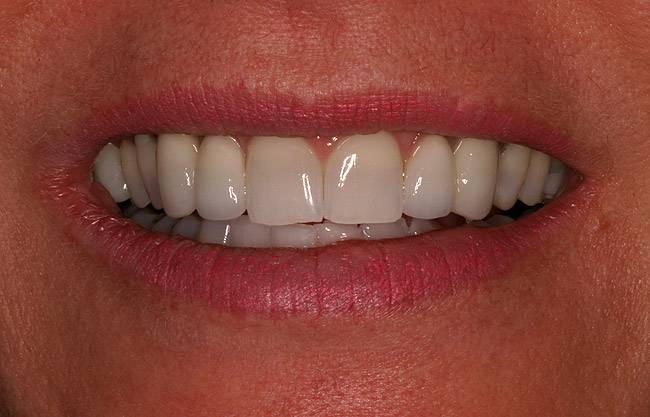

Figure 5d  Completed, porcelain-fused-to-gold implant restorations, custom gold abutments, lingual-set screw-retention, Kerr Extrude¬Æ light-body crown-abutment seal.

Figure 5d

Figure 5e  Completed, porcelain-fused-to-gold implant restorations, custom gold abutments, lingual-set screw-retention, Kerr Extrude¬Æ light-body crown-abutment seal.

Figure 5e

Figure 5f  Completed, porcelain-fused-to-gold implant restorations, custom gold abutments, lingual-set screw-retention, Kerr Extrude¬Æ light-body crown-abutment seal.

Figure 5f

Figure 5g  Completed, porcelain-fused-to-gold implant restorations, custom gold abutments, lingual-set screw-retention, Kerr Extrude¬Æ light-body crown-abutment seal.

Figure 5g